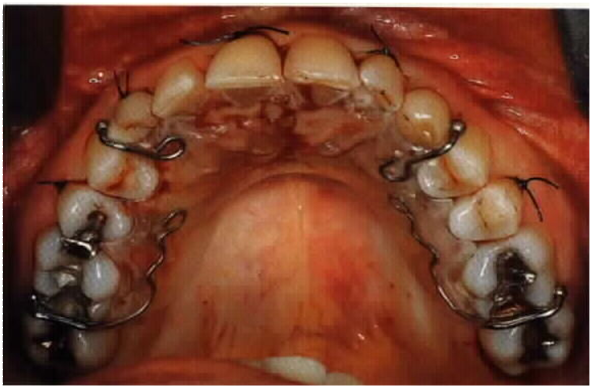

Surgery-assisted orthodontic traction

- Reflection of mucoperiosteal flap

- Crown is to be freed to its greatest circumference

- Preservation of attached ginigiva for labially and buccally placed teeth

- Orthodontic device ( button, hock and ligature wire) is to be applied

- Flap is to be then sutured back in position

- For palatal placed teeth, soft tissue excision for exposure is to be packed with whitehead’s varnish, BIPS, coepack

- Orthodontist visit to be arranged one week post op for traction application